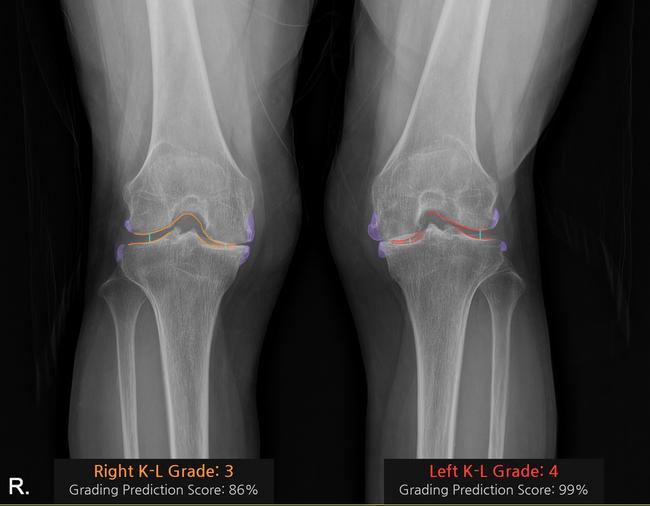

코넥티브 인공지능 관절염 판독 솔루션 '코네보 코아(CONNEVO KOA)'를 적용해 K-L grade를 판독한 사진.

병원은 AI 기반 의료 솔루션 전문 기업 코넥티브와 컨소시엄을 구성해, 무릎 관절염 진단 보조 솔루션 ‘코네보 코아(CONNEVO KOA)’를 병원 영상저장전송시스템(PACS)에 연동했다. 이번 적용은 국내 대학병원에서 AI 기반 무릎 관절염 진단 보조 솔루션이 PACS에 통합된 최초 사례다.

‘코네보 코아’는 무릎 X-ray 영상을 분석해 관절염 심각도를 K-L(Kellgren–Lawrence) 등급으로 판정하며, 골극과 관절 간격을 시각화해 제공한다. 이를 통해 진단의 일관성을 높이고 환자 상담 시 유용한 시각 자료로 활용할 수 있다. 중앙대병원은 이번 사업을 통해 영상 데이터셋 구축과 환자 평가 방법 개발을 추진, 진료 질 향상과 의료진 업무 효율화에도 기여할 계획이다.

김수진 영상의학과 교수가 총괄 책임을 맡아 솔루션의 임상적 유효성을 검증하고 시스템 고도화를 주도한다. 김성환 정형외과 교수는 “AI 솔루션이 관절염 상태를 직관적으로 보여줘 환자 이해도가 크게 향상됐다”며 “실제 사용 경험에서도 만족도가 매우 높다”고 말했다.